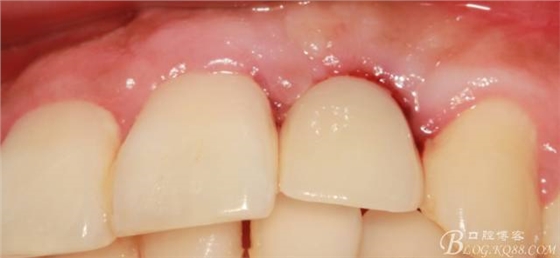

兩個月后戴入永久修復(fù)體。

戴入永久修復(fù)體當(dāng)天口內(nèi)照,雖有小瑕疵,但患者很滿意。

過程雖有曲折,時間有些長。但正是因為我的堅持不懈,正是因為我的執(zhí)著,最終取得相對滿意的結(jié)果?;颊呤翘?,患者是上帝,我不相信奇跡發(fā)生。認(rèn)真對待每一個患者,認(rèn)真對待每一個病例,遇到挫折不要等待奇跡發(fā)生,要積極主動去應(yīng)對,去解決方是制勝法寶。希望通過這個病例能給各位老師提供一點點經(jīng)驗。